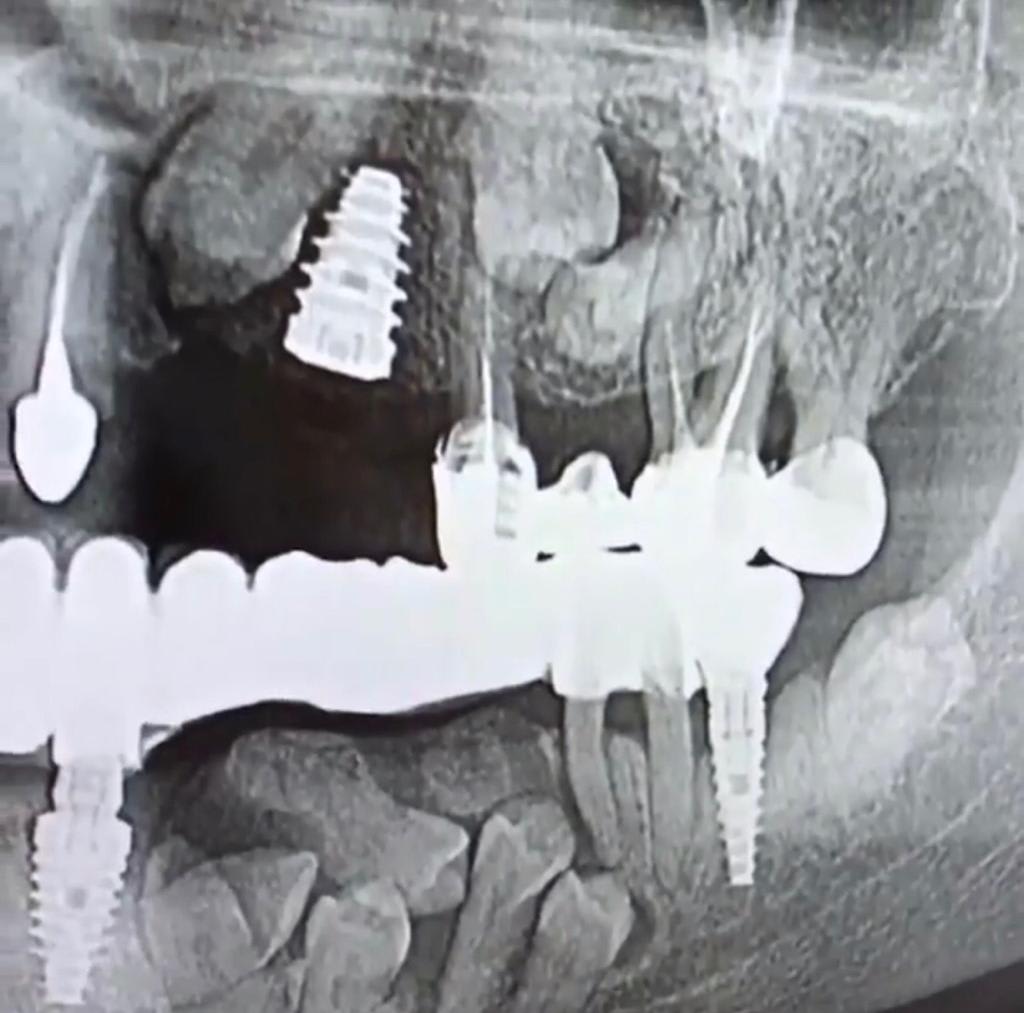

Img 20190201 wa0015 rvujht - Eugenol

Oups on voit pas le haut qui est intéressant aussi...

Img 20190201 wa0014 qcxils - Eugenol